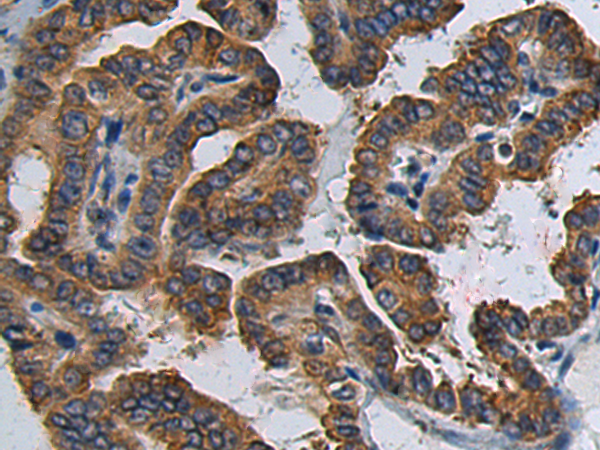

分类: 科研抗体货号: P02252别名: Snu23; Ptg-12; hSNU23应用: WB,IHC反应种属: Human, Mouse

分类: 科研抗体货号: P02212别名: APT1; LPL1; APT-1; LPL-I; hAPT1应用: WB,IHC反应种属: Human, Mouse, Rat

分类: 科研抗体货号: P02224别名: PDCR; SDR17C1应用: WB,IHC反应种属: Human, Mouse, Rat

分类: 科研抗体货号: P02251别名: ZF47; Zfp47; ZFP306; ZNF306; ZNF309; zfp-47; ZSCAN13; ZSCAN35; dJ874C20.1; dJ874C20.1应用: IHC反应种属: Human, Mouse

分类: 科研抗体货号: P02200别名: TSG应用: WB,IHC反应种属: Human, Mouse, Rat

分类: 科研抗体货号: P02223别名: CGI-24; PTD013应用: WB,IHC反应种属: Human, Mouse, Rat

分类: 科研抗体货号: P02243别名: MLN50; Lasp-1应用: WB,IHC反应种属: Human, Mouse, Rat

分类: 科研抗体货号: P02198别名: CILD18; HEATR2应用: IHC反应种属: Human

分类: 科研抗体货号: P02313别名: NA88A; HPX42B; VENTX2应用: IHC反应种属: Human

分类: 科研抗体货号: P02240别名: CIS; G18; SOCS; CIS-1; BACTS2应用: IHC反应种属: Human, Mouse, Rat